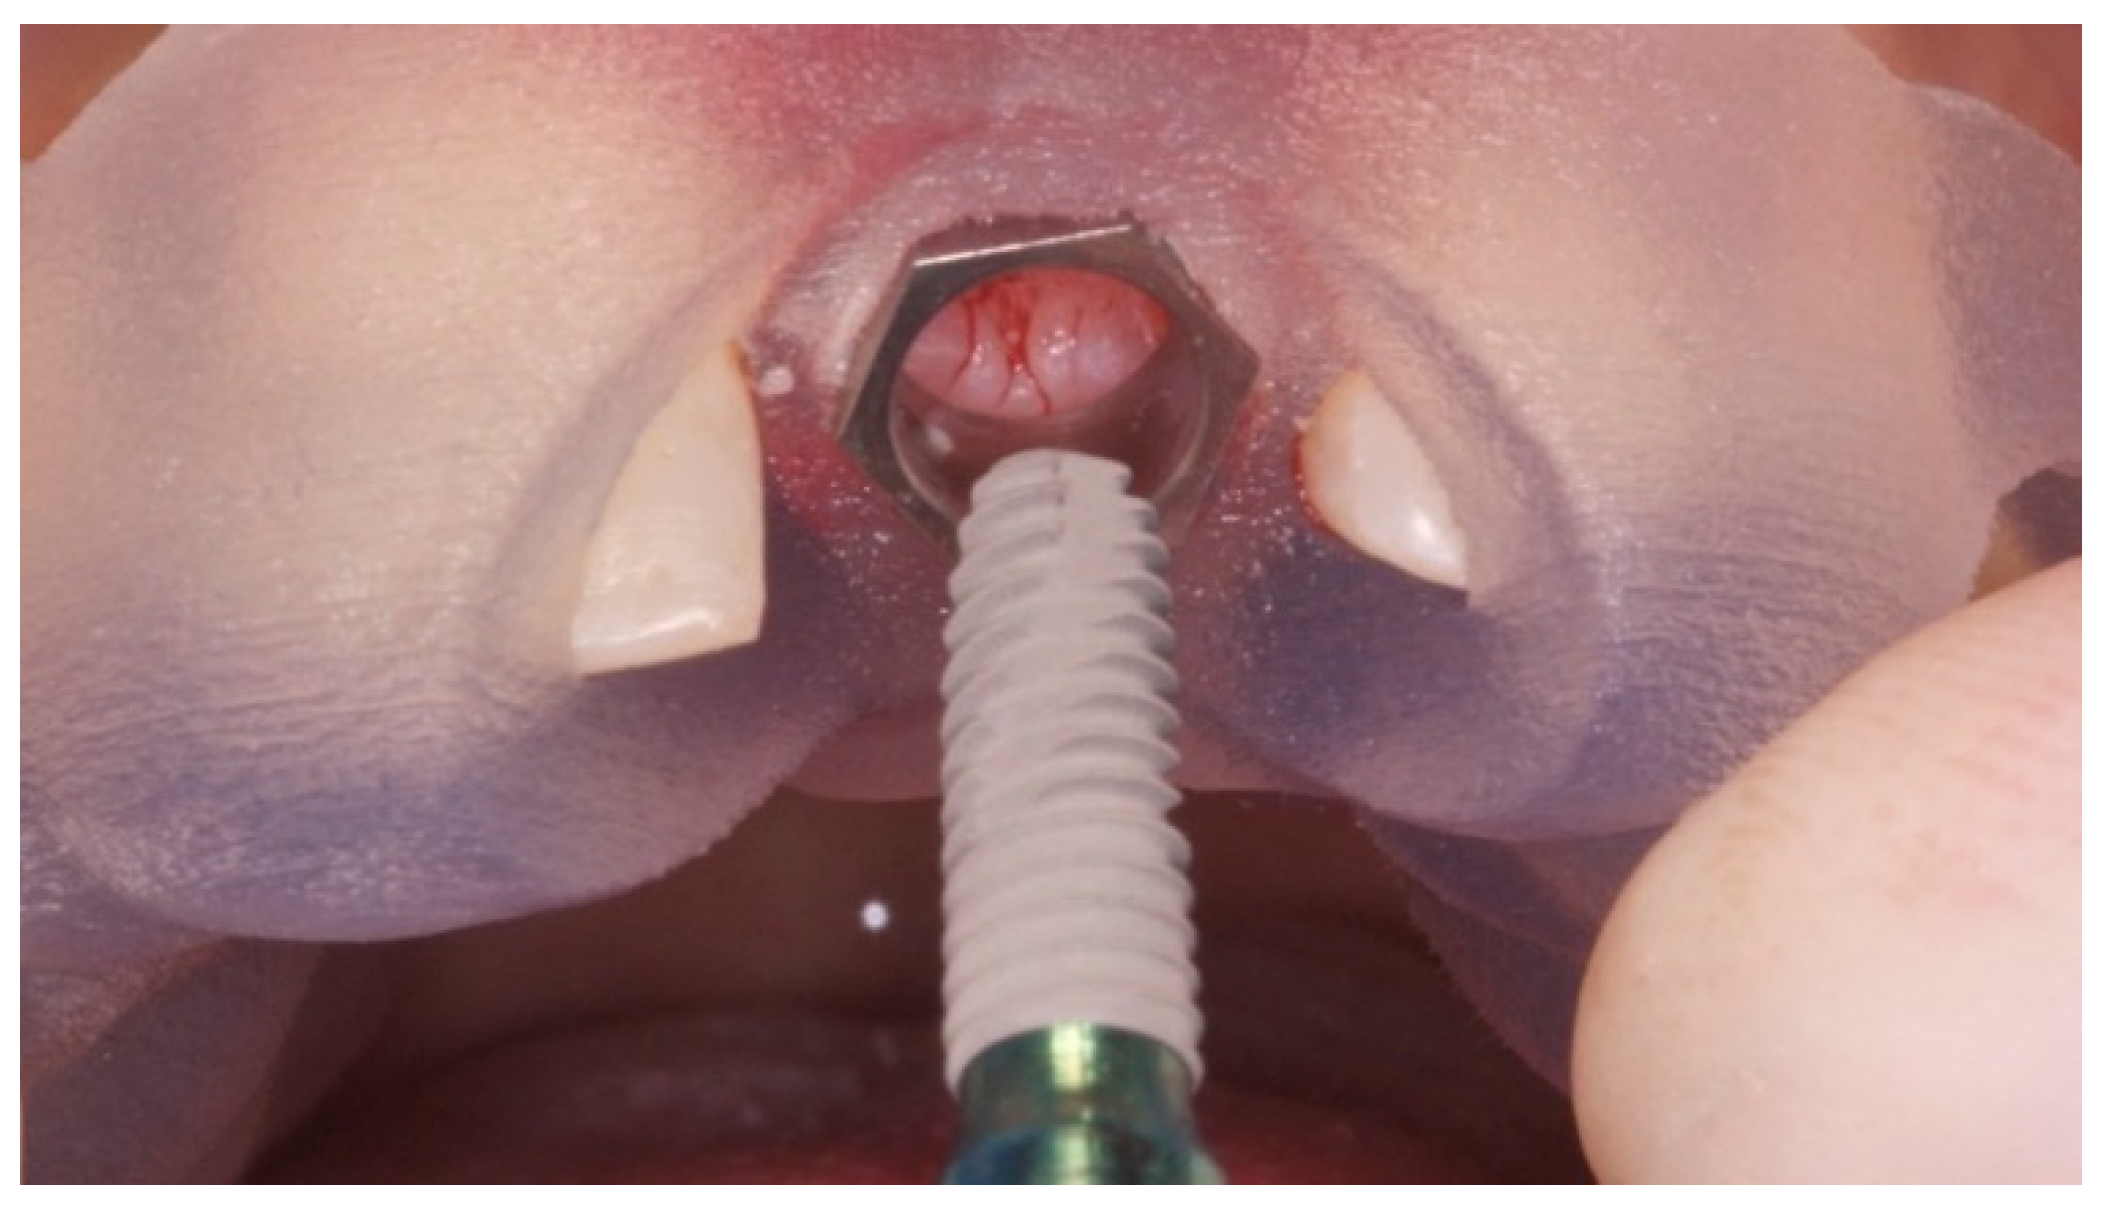

2. Case Presentation